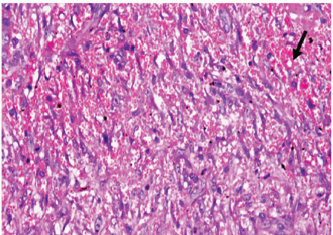

Histopathological findings of wound healing

At 7 days post wounding; the inflammatory reaction was moderate and characterized by polymorphonuclear cells and macrophages infiltration with the presence of small scab covering the wound surface. Early evidence of epithelization was detected and represented by the proliferation of epidermal epithelium under the scab. There was marked thickening and hyperplastic proliferation of epidermal epithelium at the free wound edge (Fig. 6). The dermal tissue underlying the wound area showed few polymorphonuclear cells infiltration and more abundant mononuclear cells. Fibroplasia and angiogenesis were detected in the dermis and more extensive in deeper areas of the dermis which characterized by fibroblast and angioblast proliferation forming immature young granulation tissue (Fig. 7). At 14 days post wounding, the wound area was covered by a complete layer of epidermal epithelium indicating a good epithelization rate of the wound. Proliferation of cutaneous appendages was detected. The newly formed epithelium was thick and showed partial keratinization and epithelial differentiated stratum containing polyhedral keratinocyte with the appearance of keratohyalin granules in their cytoplasm (Fig. 8). The dermal tissue showed deposition of parallel well organized and interconnected collagen bundles that arranged parallel to epidermis associated with enhanced angiogenesis represented by well-developed blood capillaries (Fig. 9). At 21 days post wounding, remodeling of the formed epithelium with relatively small scar formation and mild restoration of skin appendages. Keratinized and differentiated stratum comprising the covering epithelium and the newly formed skin appendages from the basal epidermal epithelium were detected (Fig. 10). The dermal tissue revealed well-formed organized tissue consisted of parallel compact and interconnected bundles of collagen with scant angiogenesis (Fig. 11). At 28 days post wounding, well-formed scar tissue covering highly cellular organized tissue was detected (Fig. 12). The dermal tissue revealed well-arranged compact collagen bundles containing scarce blood vessels (Fig. 13).

Fig. 8. Skin of a goat from electroacupuncture group at 14 days post wounding showing enhanced reepithelization evidenced by differentiated polyhedral keratinocytes in the stratum spinosum and keratohyalin granules in the stratum granulosum (arrow) and keratinization (arrow head), (HE ×100).

Fig. 9. Skin of a goat from electroacupuncture group at 14 days post wounding showing well organized and interconnected collagen bundles that arranged parallel to each other and to epidermis (arrow head) associated with enhanced angiogenesis represented by well-developed blood capillaries (arrow), (HE ×200).